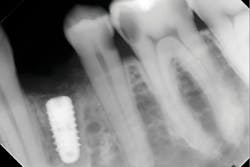

Another reason immediate placement is advantageous is that once the extraction is complete, the hole is usually already in the proper place for the implant. You may have to redirect your osteotomy slightly palatally, mesially, or distally, but the socket serves as an excellent guide for placement. In some cases, especially premolars, you can use an implant with aggressive threads to place without any osteotomy at all. You can engage the mesial and distal walls to achieve primary stability. This greatly shortens the appointment time, lowers risk, and increases patient satisfaction. Figures 1 and 2 show a MorsTorq in site No. 21 that was placed after an atraumatic extraction during my most recent two-day Louisiana Implant Institute course. Note the sharp threading on the MorsTorq, which allows for optimized immediate placement performance.There are some circumstances where immediate placement is not desirable. If the socket is too large to engage the mesial and distal walls and vital anatomical structures are located just apical to the socket, immediate placement is not recommended. Chronically infected sites also present a higher risk for immediate placement. If you can completely rid the socket of all soft tissue and the patient has the appropriate antibiotics onboard, it is possible. However, most of these cases are more predictably treated with early placement (waiting four to six weeks without grafting) or delayed placement (three to six months with grafting).